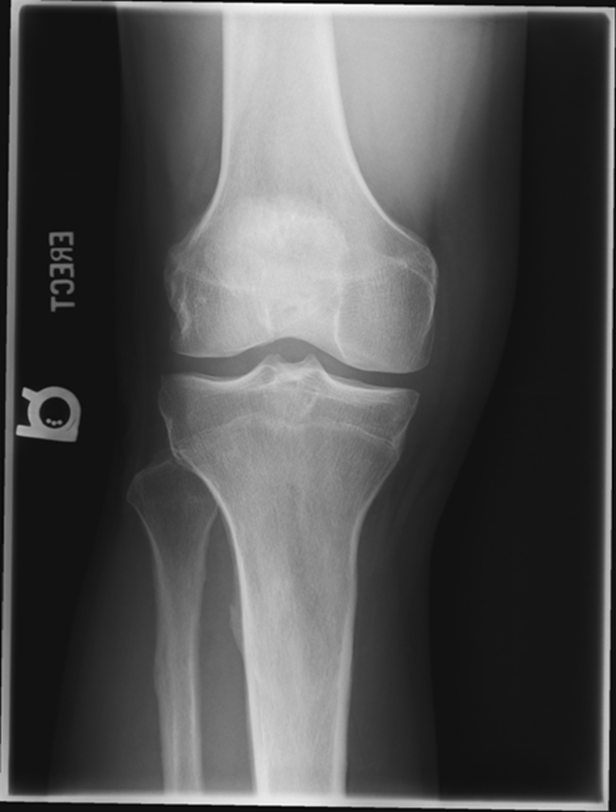

Non Trauma PA Erect (RH)

(patient age 40 and older)

•Evidence of proper collimation and the presence of a side marker placed clear of the anatomy of interest

•Both knees without rotation (RH only does the side of interest)

•Knee joint spaces centered to the exposure area (RH only does the side of interest)

Bony trabecular detail and surrounding soft tissue

Repeat for not enough exposure -3.6

Increase Density by 2

Fix centering

joint space is narrowed off, condyles look symmetric

platues look equal

slight superimposition of tibia/fibula

GOOD IMAGE repeat for exposure index